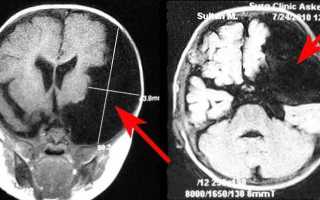

Диагностика кисты мозжечка

- Магнитно-резонансная томография (МРТ). Этот метод позволяет получить детальные снимки мозга и мозжечка, что помогает выявить наличие и размеры кисты, а также определить ее тип;

- Компьютерная томография (КТ). Исследование позволяет получить рентгеновские снимки мозга и мозжечка с использованием рентгеновского излучения и компьютерной обработки данных. Оно помогает оценить структуру мозга и выявить наличие кисты;

Киста мозжечка может быть обнаружена случайно при проведении МРТ или КТ-обследовании головы. В большинстве случаев она не проявляет никаких симптомов и не требует лечения. Однако в некоторых случаях она может вызывать различные проблемы и требовать медицинского вмешательства.